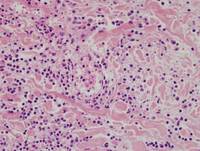

Figure 2: H&E in Hydroa Vacciniforme-like Lymphoproliferative Disorder

Features seen in the images below:

1. Epidermal degeneration with spongiotic vesiculation

2. Lymphoid infiltration in dermis and subcutaneous tissue

3. Periadnexal and perivascular infiltration by small-to-medium sized neoplastic cells without significant atypia